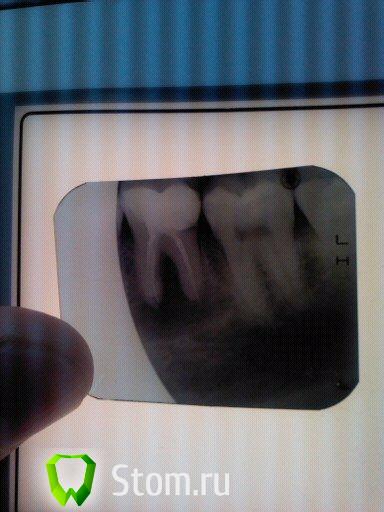

ARislanV Опубликовано 14 февраля, 2012 Поделиться Опубликовано 14 февраля, 2012 Можете,если не сложно,снимок Вашего фрукта вывесить?А вот и помелла))) 46з. Ссылка на комментарий

samsonov Опубликовано 14 февраля, 2012 Поделиться Опубликовано 14 февраля, 2012 А вот и помелла))) 46з.http://forum.stom.ru/topic/17755-nikakih-posplombirovochnih-bolei/page__st__20по -соседству тут созвучно немного....Есть ощущение в моих старых окулюсах ,что в медиальном корне металлический фрагмент.А так , 99%- зуб перелечится успешно надеюсь.В дистальном поискать второй...УДАЧИИиииии Ссылка на комментарий

ARislanV Опубликовано 16 февраля, 2012 Поделиться Опубликовано 16 февраля, 2012 (изменено) http://forum.stom.ru...ei/page__st__20по -соседству тут созвучно немного....Есть ощущение в моих старых окулюсах ,что в медиальном корне металлический фрагмент.А так , 99%- зуб перелечится успешно надеюсь.В дистальном поискать второй...УДАЧИИиииииКаналы прочистили, в дистальном нашли второй. Закачали метапекс, инструмента вроде не было. Доктор, а где тут у Вас протейперы? Я если честно не вижу нормального прохождения каналов до apex'a и кстати мыть после гипохлорида, хлоргексидином не очень вроде. Реакция между ними.Да, в медиальном похоже инструмент. Но лучше еще пару снимковПротейперы были, корни короткие 18 мм от жеватки, получилось то что получилось. Промывать хлоргексидином 0.1% !? - думаю уж лучше водой, хотя бы само обмана не будет. Под этими пломбами можно ещё кариес нарыть.Или эти пломбы глубоко под десну уходят.Поэтому лучше сначала всё старое убрать,не полениться и сделать преэндо.Так надёжней и на душе спокойней .Да + по тому что остается от тканей зуба, пациенту уже сразу можно сказать, что там будет пломба или коронка. Изменено 16 февраля, 2012 пользователем ARislanV Ссылка на комментарий

Heineken Опубликовано 16 февраля, 2012 Поделиться Опубликовано 16 февраля, 2012 Каналы прочистили, в дистальном нашли второй. Закачали метапекс, инструмента вроде не было.RE Мне кажется у Вас проблеме больше в медиальном. Попытался отметить на снимке, где вижу её. Ссылка на комментарий